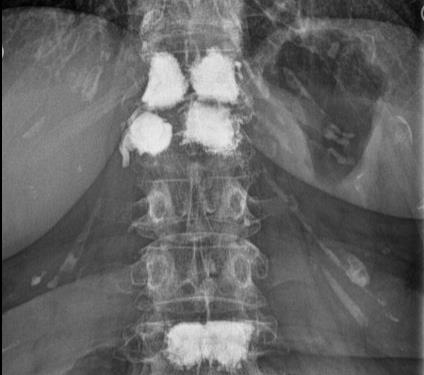

Osteoporose kann verschiedene Ursachen haben. Die Erkrankung ist jedoch dank fortschrittlicher Medizin gut behandelbar. Zur Diagnose und Abschätzung des Knochenbruchrisikos erfolgt eine genaue Befragung (Anamnese), eine klinische Untersuchung mittels neuester Geräte zur Knochendichtemessung und bei Bedarf auch Gewebeuntersuchungen des Knochens (Knochenbiopsie). Mittels dual energy x-ray absortiometry (DXA) wird die Knochendichte bestimmt.

Zudem sind die Bestimmung des TBS (trabecular bone score) zur Abschätzung der Mikroarchitektur des Knochens und eine Messung der Gesamtzusammensetzung des Körpers (Knochen- und Muskelmasse, Fettanteil) möglich. Neben der Knochendichtemessung können die für den Knochenstoffwechsel wichtigen Blutwerte bestimmt werden.